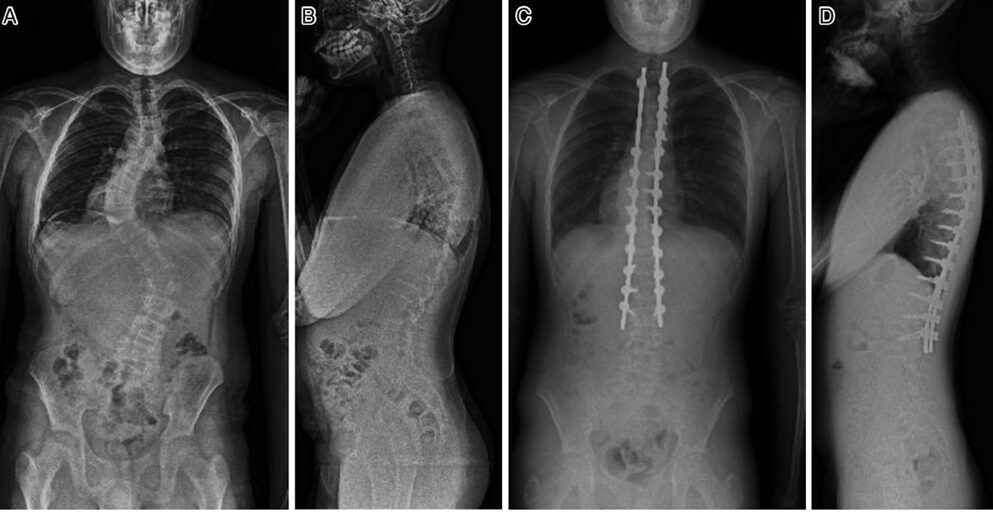

図:症候性側弯症に対して手術前後のレントゲン写真

出典:須藤 英毅. (2025). 4D 解剖学的矯正. 整形外科 Surgical Technique, 15(1)

手術療法

弯曲が重度 (胸椎カーブでは45-50度以上、腰椎カーブでは35-40度以上)で、進行が予想される場合や、保存療法で効果が得られず、痛みや機能障害が著しい場合に検討されます。手術の目的は、背骨の湾曲を矯正し、固定することで、見た目の改善、痛みの軽減、呼吸機能の維持・改善を図ることです。主に、脊椎固定術が行われます。